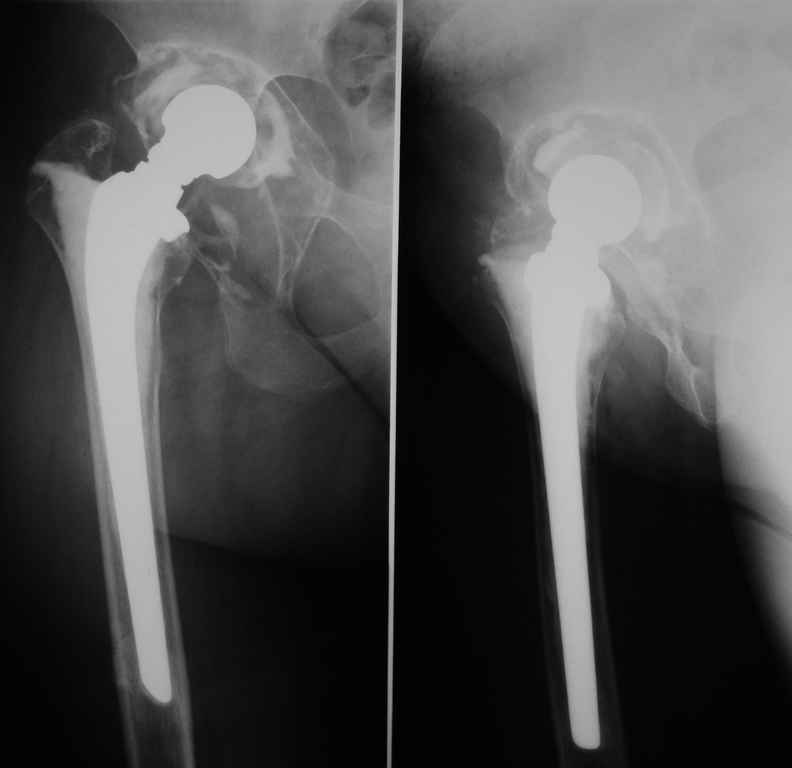

Больная 40 лет, поступила в отделение с диагнозом: Нестабильность чашки цементного эндопротеза Мовшовича правого тазобедренного сустава с протрузией тазового компонента.

An.morbi: В 1991 г.ДТП, получила ушиб правого тазобедренного сустава, после чего стали беспокоить периодические боли в правом тазобедренном сустав при нагрузке. В 1992 г. Госпитализирована в ГВКГ им. Бурденко с артрозо — артритом правого тазобедренного сустава, предположительно туберкулезной этиологии, в течение года получала спецефическую терапию (стрептомицин, тубазид, рифацин, канамицин, пиразинамид) Туберкулезный процесс перешел в стадию затихания с формированием метатуберкулезного фиброзного анкилоза, БК- (минус). В 1993 г эндопротезирование правого тазобедренного сустава цементным эндопротезом Мовшовича. Послеоперационный период протекал гладко, получала курс восстановительной терапии. В 2004 г. снята с учета в туберкулезном диспансере. В конце 2004 года появились периодические боли в правом тазобедренном суставе при физической нагрузке. С 2005 г. ходит с тростью.

Рентгенограммы от 07,07,2009г.

Данных за нестабильность ножки не выявлено.Помогите определиться с выбором оптимального варианта ревизии: